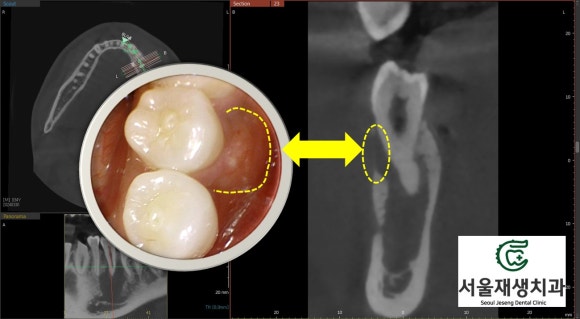

치료 시작하고 두 달 남짓 지났을 무렵...

신경치료를 시작하고 한 두 달 정도 지나면,

CT를 통해서 뼈의 재생 여부를

관찰할 수 있습니다.

이 환자분은 두 달 정도 되었는데요,

한 번 CT를 찍어볼까요?

![[치외치신경치료] 뿌리 끝 염증이 커서 발치해야된대요! 치아 머리에 볼~록! 알고보면 무서운 작은 혹 (서울재생치과) 관련 이미지 19](https://pub-9f2bb3498faf4d1d8714b41df24753e3.r2.dev/content/clinics/archive/nqmm0udu86/naver_blog/honeybeevuvu/assets/by_hash/06f6bb597a645324562c2dcd3b7ed8416d8442eea8b2f1a2295f2e40049af2c4.jpg)

꽤나 드라마틱한 변화!!!

잘 모르시겠다구요?

![[치외치신경치료] 뿌리 끝 염증이 커서 발치해야된대요! 치아 머리에 볼~록! 알고보면 무서운 작은 혹 (서울재생치과) 관련 이미지 20](https://pub-9f2bb3498faf4d1d8714b41df24753e3.r2.dev/content/clinics/archive/nqmm0udu86/naver_blog/honeybeevuvu/assets/by_hash/3ee73b4a70f6df6e42f4c25d24593391de91da23d380daed9f89783da5d8f5bd.jpg)

노란색으로 표시된 부위가

새로이 뼈가 재생된 공간입니다.

신생골은 아직 석회화가 부족해서

초기엔 옅은 회색으로 보인답니다.

이정도면 아주 충분합니다!

다음 달에 치료를 마무리합시다~^^